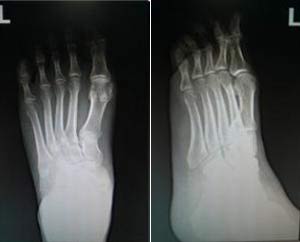

(图:曾先生来院时左足有许多细小痛风石)

体格检查:血压130/80mmHg,中心性肥胖,左足第一跖趾关节红肿热痛,灼痛拒按,足背有少量痛风石,皮温升高,触痛(+)。

(图:曾先生左足的X光可以看出明显痛风石)

杜爱华主任看了检查报告后,结合曾先生的身体情况,给他制定了一套针对性的科学方案,并当天就为他治疗。治疗结束后,曾先生感觉左足趾关节疼痛减轻不少,整个人轻松了许多。在经过两个疗程的治疗,曾先生的左足关节疼痛感消失,红胀症状消退,痛风石溶解,关节无压痛感,行走自如,活动能力恢复。